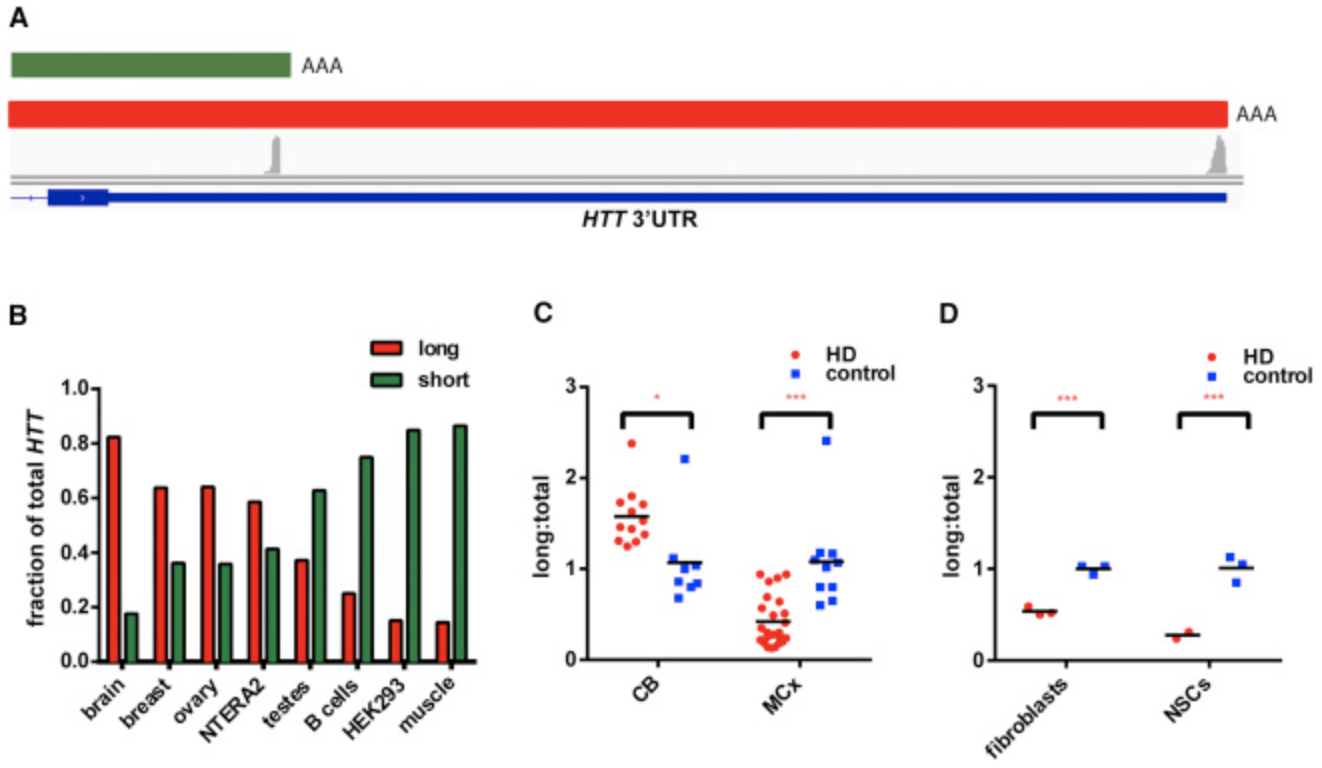

SEPTEMBER 26, 2017, New publication from the Aronin lab. Alterations in mRNA 3' UTR Isoform Abundance Accompany Gene Expression Changes in Human Huntington's Disease Brains. Romo L, Ashar-Patel A, Pfister E, Aronin N. Cell Rep. 2017 Sep 26;20(13):3057-3070. doi: 10.1016/j.celrep.2017.09.009

SEPTEMBER 26, 2017, New publication from the Aronin lab. Alterations in mRNA 3' UTR Isoform Abundance Accompany Gene Expression Changes in Human Huntington's Disease Brains. Romo L, Ashar-Patel A, Pfister E, Aronin N. Cell Rep. 2017 Sep 26;20(13):3057-3070. doi: 10.1016/j.celrep.2017.09.009